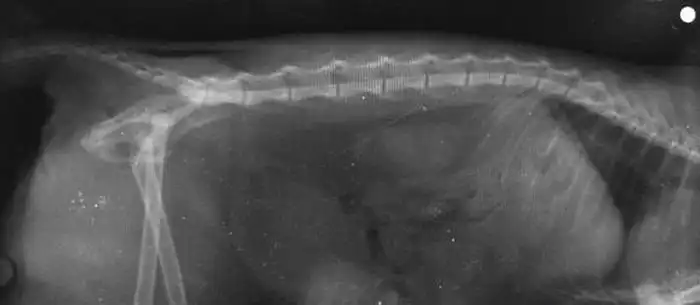

Страшный, но не понятный мне, снимок даст понять врачам, какие шансы выжить у кошки.

Тут доктор пишет непонятным почерком о переломах в тазу и отрыве чего-то там. Звучит страшно. Прогноз не очень — сказали, что вряд ли будет ходить, а гипс наложить нельзя.